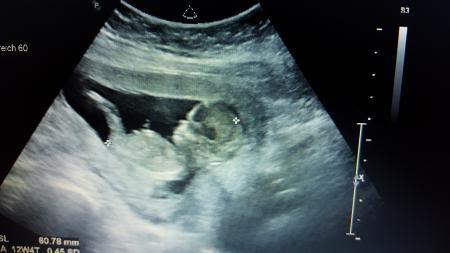

Guten tag ihr lieben Ich habe heute von meinen Fa ein vorsichtiger 80% iges Jungen outing bekommen. Ich habe von der nub Theorie gelesen, weiß aber nicht ob meine bilder dafür geeignet sind. Letztlich ist es egal was es wird weil das wichtigste ist das es gesund ist, aber wir haben drei Mädchen und es wäre für uns ein Wahnsinn wenn wir jetzt wirklich einen jungen bekommen würden.

Ich habe noch ein zweites Bild